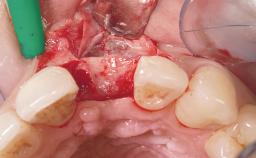

Late Flapless Placement of an Implant in a Maxillary Left Central Incisor Site

A 39-year-old male patient presented with a chief complaint of discomfort and gingival discoloration around his maxillary left central incisor. He was in good general health and was a non-smoker. His past dental history was significant because of the traumatic fracture of tooth 21 in a sporting accident at age 13. Initial dental treatment included endodontic therapy and a full-coverage restoration. The patient became symptomatic 5 years later, when structural failure of the tooth resulted in the dislodgment of the crown. Endodontic retreatment, apical surgery, and post-and-core restoration were performed.

Bone Volume Deficient horizontally, requiring prior grafting